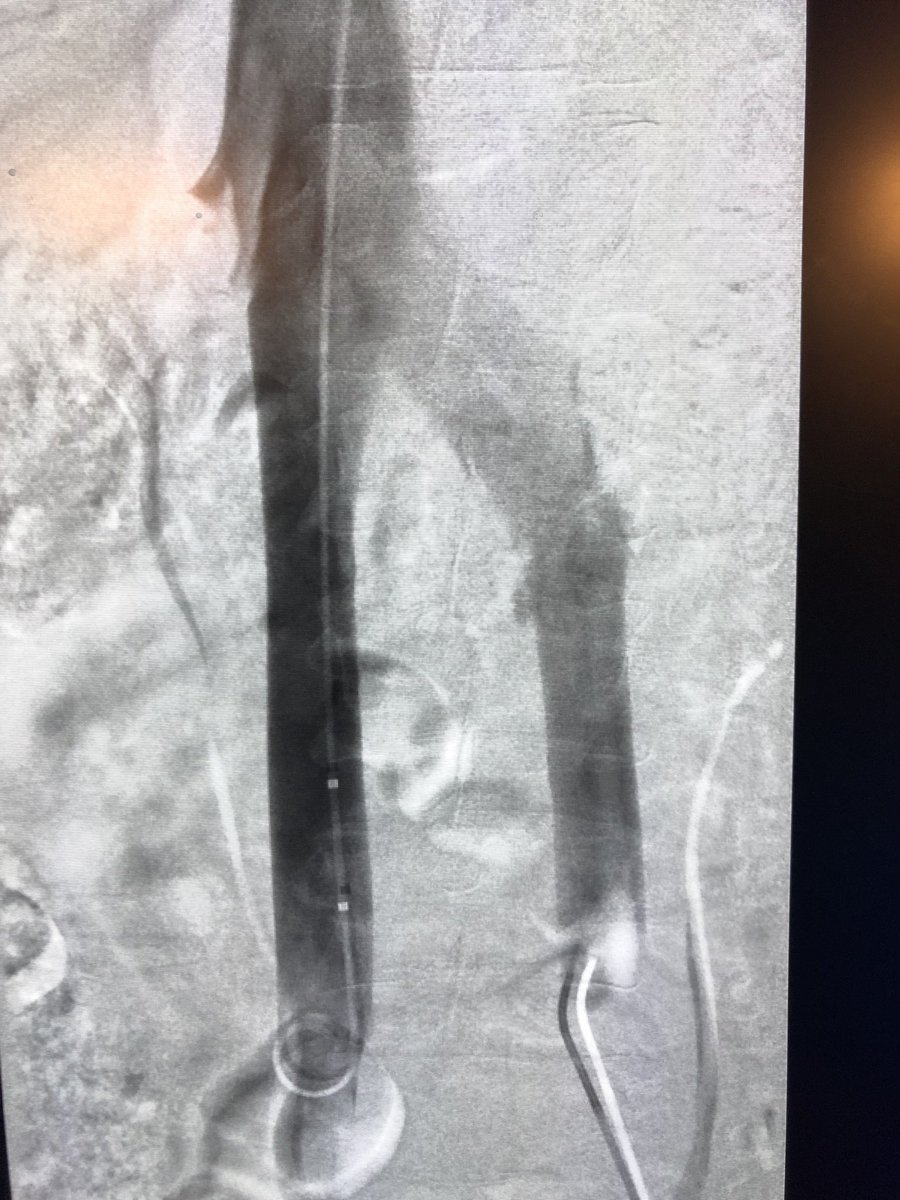

This patient presented with severe leg edema, iliocaval thrombus with 12 year old #IVCfilter. After a night of lysis a large vol of chronic appearing clot persisted. Was able to get most of it out with a few passes with the Inari T20 from popliteal access. #iRad

10

62